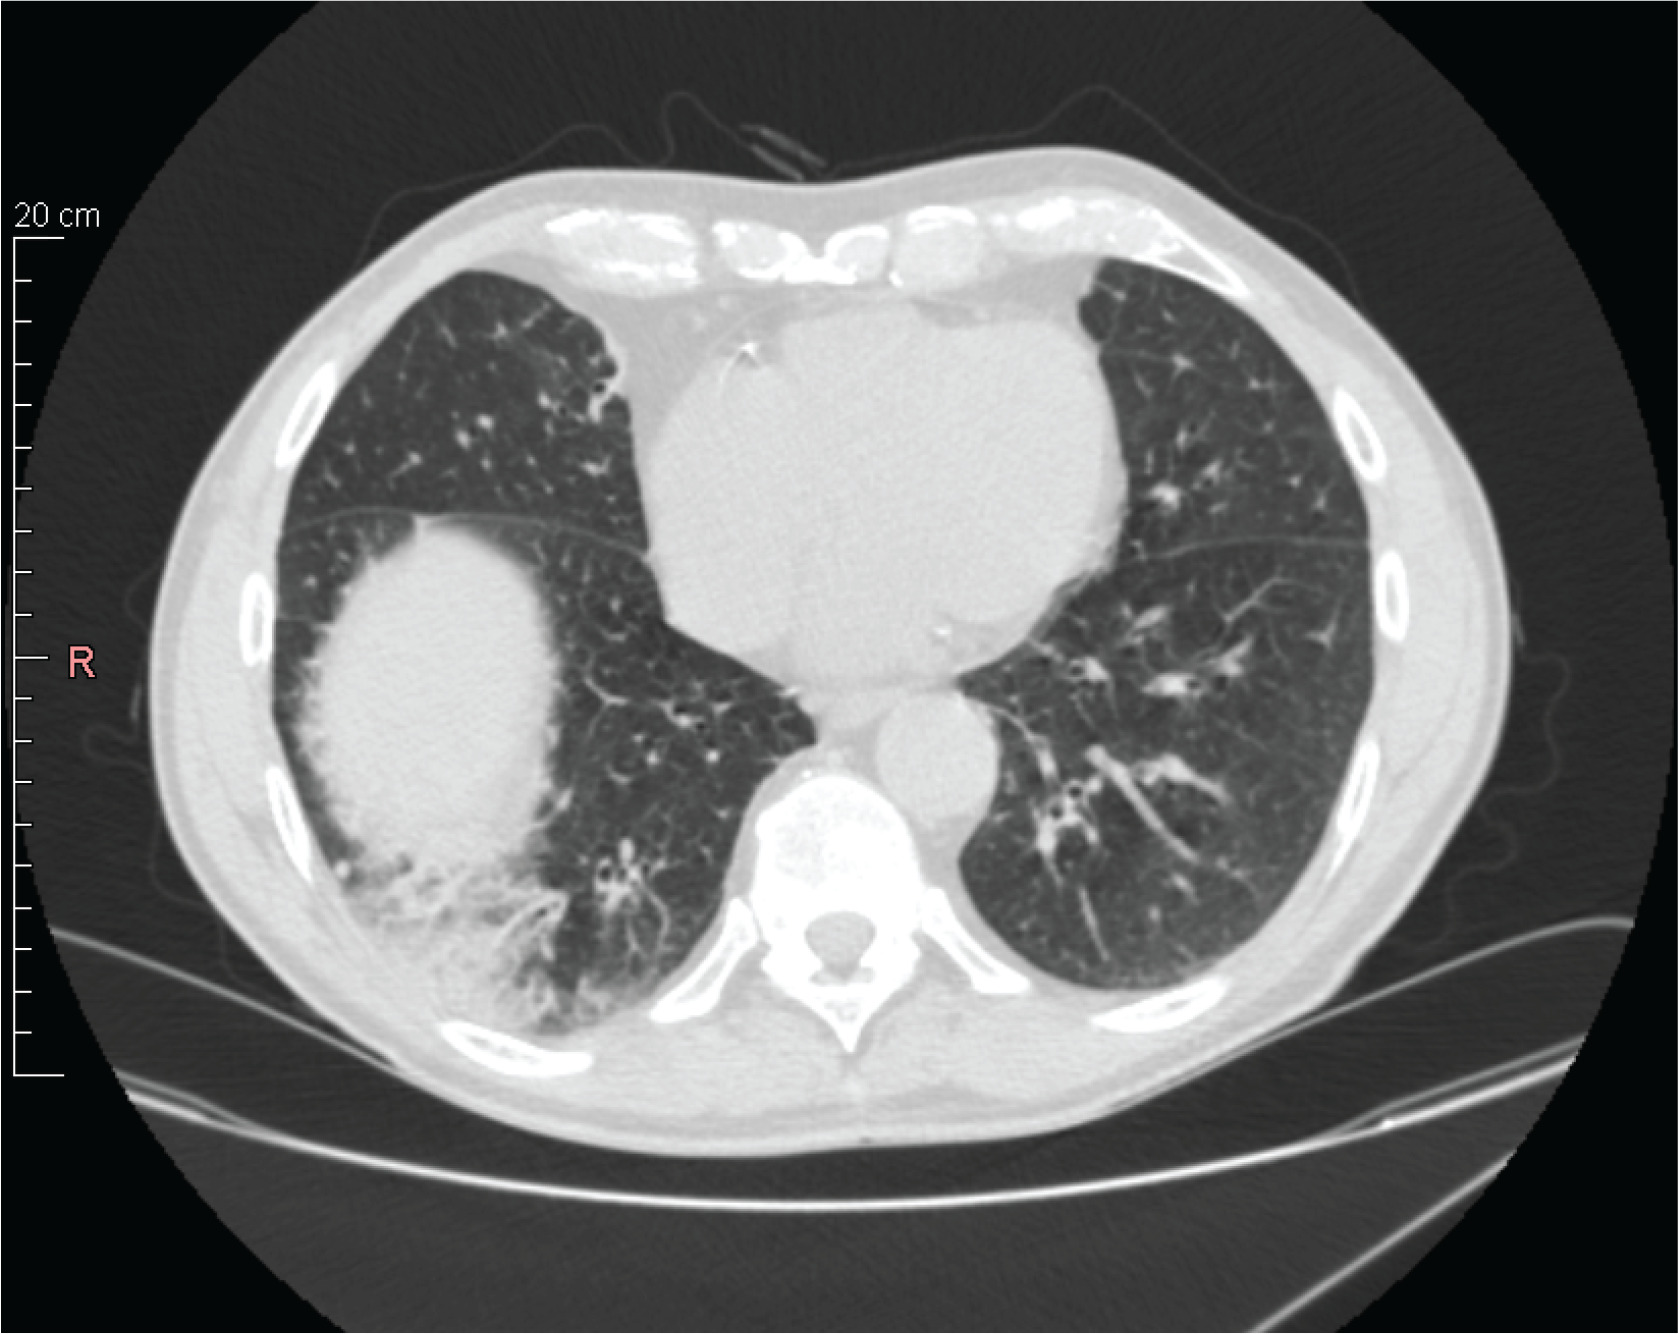

Figure 1

Chest high-resolution computed tomography before treatment. Chest high-resolution computed tomography showing peripheral ground-glass opacities with thickening of the interlobular septa

A 65-year-old Caucasian male with a medical history of hypertension, prostatic hypertrophy, and duodenal ulcer disease was admitted to the pulmonology department for the evaluation of a persistent non-productive cough lasting approximately six months, alongside reported weight loss and decreased exercise tolerance. High-resolution computed tomography (HRCT) demonstrated peripheral ground-glass opacities with thickening of the interlobular septa, bilateral bronchial dilation, and small tumor lesions (Figure 1). Laboratory findings revealed significant eosinophilia in peripheral blood (53.8%) with leukocytosis (13.4 G/L). Diagnostic bronchoscopy with bronchoalveolar lavage (BAL) was performed, during which biopsies of papular lesions on the bronchial walls were taken. Bacteriological cultures, including testing for acid-fast mycobacteria and fungi, were conducted, revealing negative results for Aspergillus fumigatus antigens and antibodies. Histopathological examination indicated mild inflammation with a few eosinophils and no evidence of neoplasia. Cultures from the BAL fluid were also negative. To rule out common causes of eosinophilia, stool tests for parasites were performed, yielding negative results; however, antiparasitic treatment was initiated due to potential false negatives. An extensive autoimmune workup, including various autoantibody tests, returned normal results. Serological tests for atypical bacterial infections were conducted, with borderline results for Bordetella pertussis leading to treatment with clarithromycin; other bacterial infections were excluded. Echocardiography suggested cardiomyopathy, with further cardiac evaluations scheduled based on potential endocardial involvement. Given the pronounced eosinophilia, steroid therapy was initiated, resulting in a significant reduction in eosinophil levels to 1.3%. Three weeks later, BAL revealed that 85% of collected cells were eosinophils. Diagnosis of hypereosinophilic syndrome was established, and treatment with prednisone at 40 mg/day commenced. After one month, a follow-up chest radiograph indicated regression of peripheral nodular shadows and ground-glass opacities, with bilateral pericardial fibrosis. Pulmonary function tests revealed no abnormalities, and inflammatory markers in biochemical tests were negative, with no irregularities in the peripheral blood smear. Follow-up HRCT showed regression of interstitial changes. A decision was made to gradually reduce the prednisone dosage to 10 mg for 14 days, subsequently decreasing to 5 mg for another 14 days before cessation. Three months after stopping prednisone, eosinophilia re-emerged. Repeat bronchoscopy with BAL was performed, and a hematology consultation was scheduled to exclude clonal eosinophilia, which was ruled out, alongside cardiac MRI. Prednisone was reinstated at a maintenance dose of 5 mg/day, as attempts to taper led to recurrent eosinophilia. The patient exhibited a favorable response to treatment, with regression of radiological changes; however, treatment was complicated by recurrent infections. The patient continues to be monitored for any recurrence of infiltrates or eosinophilia upon dose reduction or discontinuation of glucocorticoids. No significant impairment of lung function was noted based on spirometry, body plethysmography, DLCO, and the 6-minute walk test. Secondary causes of eosinophilia were excluded, leading to a diagnosis of idiopathic chronic eosinophilic pneumonia. Due to the high risk associated with long-term systemic glucocorticoid therapy, a request for mepolizumab treatment was submitted and approved. Subsequent treatment with subcutaneous mepolizumab at 300 mg every four weeks commenced, with the goal of tapering or discontinuing systemic steroids. After two months, systemic steroid treatment was completely halted. Follow-up HRCT six months after starting mepolizumab showed improvement in interstitial and ground-glass opacities in both lungs (Figure 2). Follow-up laboratory work showed eosinophilia level 1.1%, WBC 4.7 G/L and CRP 1.0. He successfully weaned off steroids and has continued on mepolizumab 300 mg monthly dosing with maintained clinical improvement in symptoms. The patient has remained free of disease recurrence to date (over one year). The patient presents to the department every month for drug administration, during which routine laboratory tests are performed, including blood eosinophil level assessment (Figure 3). Additionally, the patient undergoes periodic chest X-ray examinations for monitoring purposes. The medication is well tolerated, and the patient reports no adverse effects. Furthermore, the patient reports an improvement in quality of life, with a decreased frequency of infections and no need for chronic corticosteroid therapy.